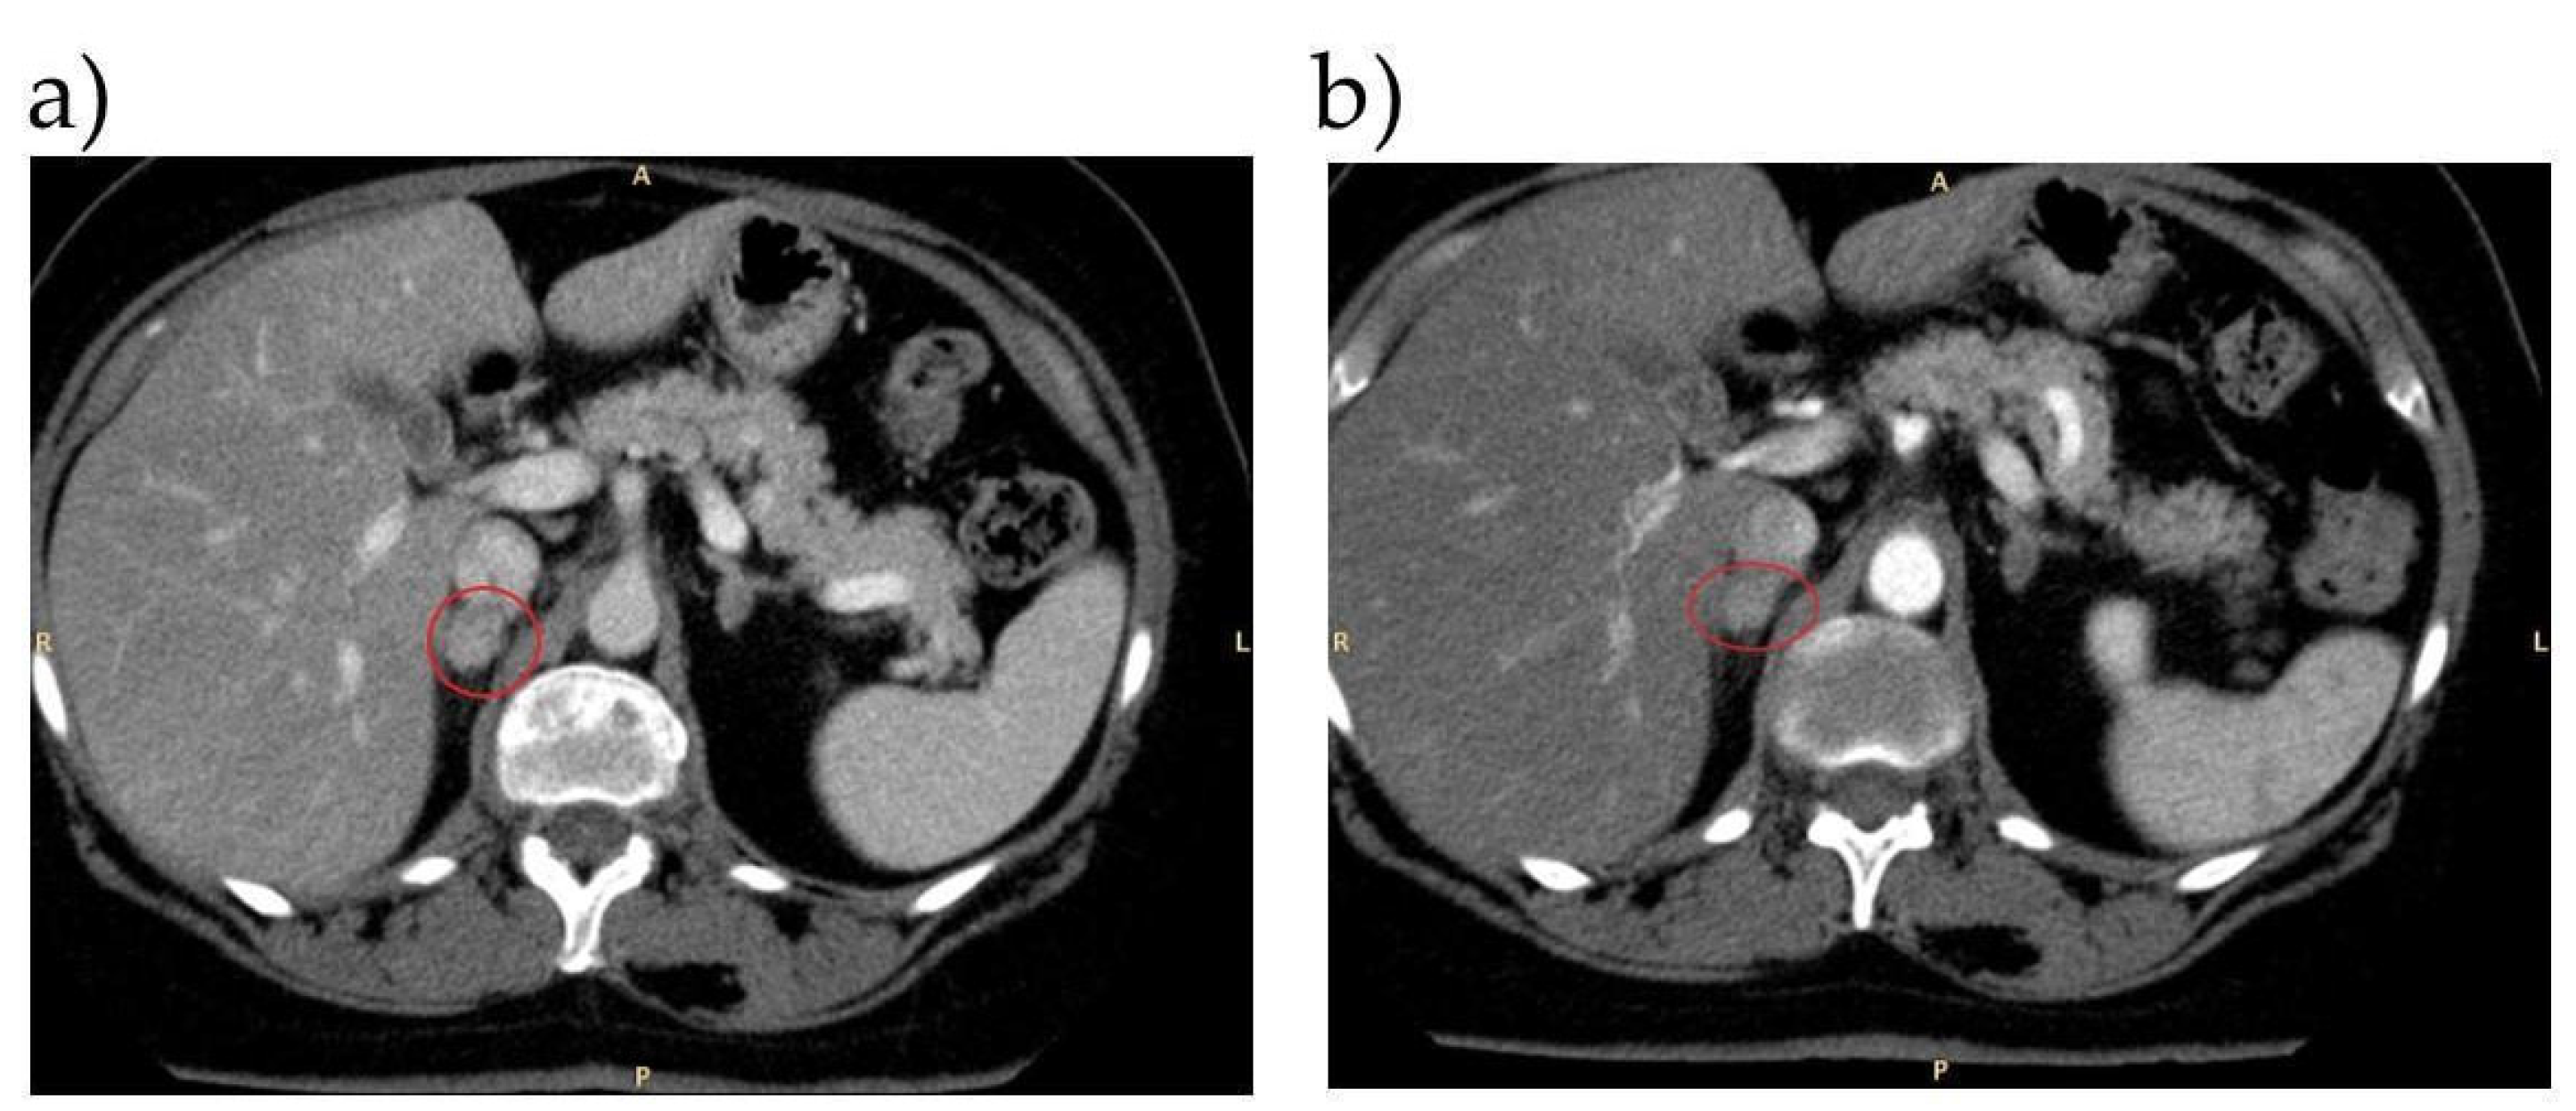

5.1. Case 1

Does True Unilateral PA Exist?

| 1 | SIT and CCT: both positive | Left adrenal adenoma | Left-sided aldosterone lateralization | Left adrenalectomy | Good control of BP on Olmesartan therapy, renin levels no more suppressed 6 months after surgery |